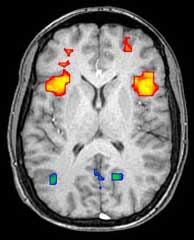

Axial MRI slice at the level of the basal ganglia, showing fMRI BOLD signal changes overlayed in red (increase) and blue (decrease) tones.

ويمكن للتصوير الوظيفي، على سبيل المثال، معالجة المعلومات عن طريق مراكز في المخ ليتم تصويرها مباشرة. مثل معالجة المنطقة المصابة في المخ والمسئولة عن زيادة الأيضا والتي تظهر مضيئة في المسح. وأحد الاستخدامات المعرفية للتصوير الوظيفي هي استخدامه في التعرف على الأفكار أو قراءة الفكر.